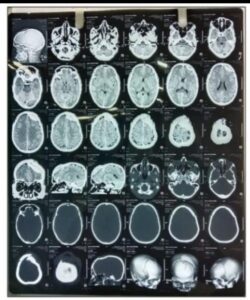

डीजे न्यूज, गिरिडीह : गिरिडीह के स्वास्थ्य इतिहास में एक नया अध्याय जुड़ गया है। मर्सी हॉस्पिटल, गिरिडीह में पहली बार न्यूरो सर्जरी (मस्तिष्क की शल्य चिकित्सा) सफलतापूर्वक संपन्न की गई। यह उपलब्धि न केवल अस्पताल के लिए बल्कि पूरे जिले के लिए गर्व का विषय है, क्योंकि अब गिरिडीह के मरीजों को ऐसी जटिल सर्जरी के लिए रांची, धनबाद या पटना जैसे बड़े शहरों की ओर रुख नहीं करना पड़ेगा।

मरीज को गंभीर सिर की चोट और खोपड़ी में फ्रैक्चर था। स्थिति अत्यंत नाजुक होने के बावजूद, मर्सी हॉस्पिटल के अनुभवी चिकित्सकों की टीम ने उच्च स्तरीय चिकित्सा उपकरणों और आधुनिक तकनीकों की सहायता से यह ऑपरेशन सफलता पूर्वक पूरा किया। वर्तमान में मरीज की स्थिति स्थिर है और वह स्वस्थ होने की दिशा में तेजी से अग्रसर है।